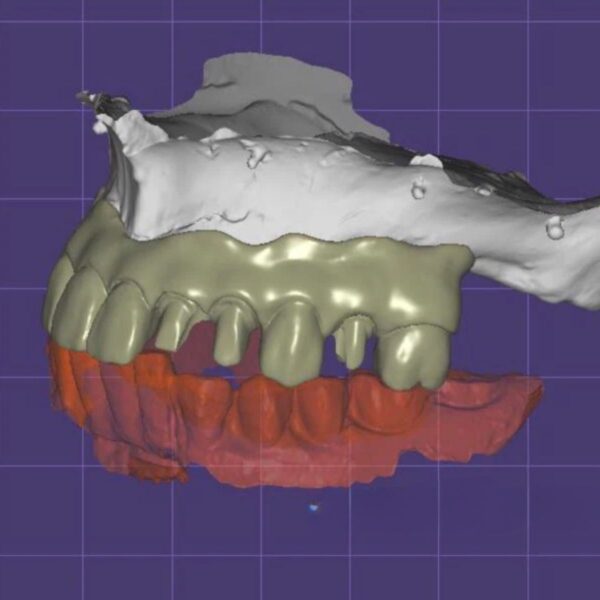

China Dental Design Complex Case Gallery

Challenging Projects That Showcase Our China Dental Design Expertise

Dental Crown Design

Implant Crown Design

Dental Model and Denture Design

- Full mouth rehabilitations

- Multi-unit implant bridges

- Aesthetic zone reconstructions